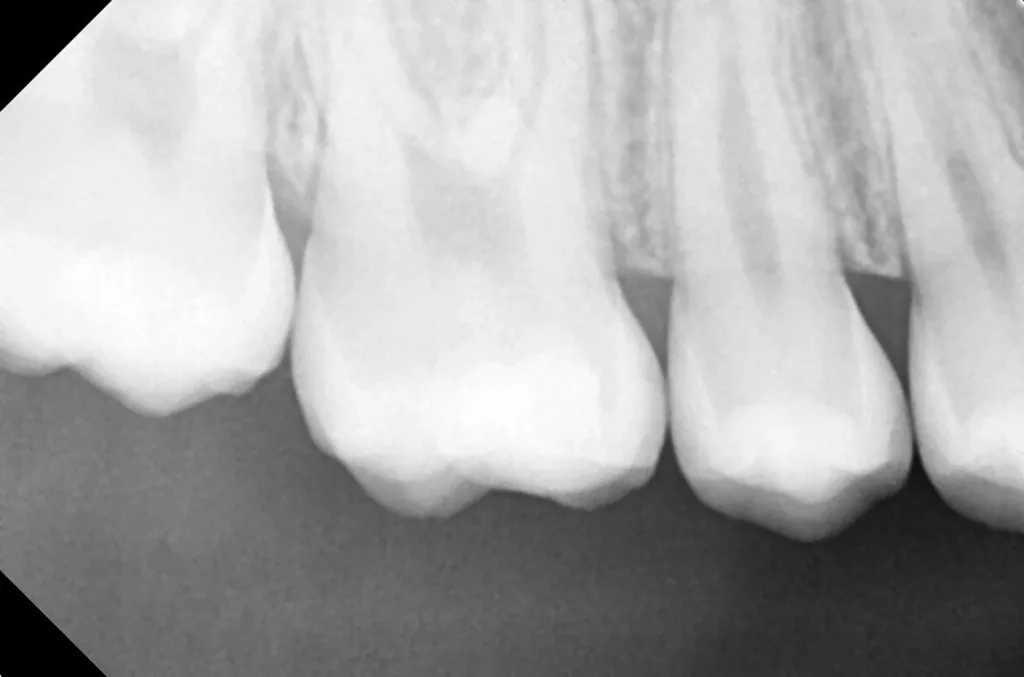

Bei routinemäßigen Röntgenkontrollen ergeben sich manchmal Zufallsbefunde unklarer Genese. So stellt sich beispielsweise bei der Betrachtung der Abbildung 1 die Frage, wie sich ein Zahnhartsubstanzdefekt so schnell entwickeln konnte. Ein weiteres Röntgenbild (Abb. 2), das vor dem Zahndurchbruch aufgenommen wurde, zeigt jedoch, dass es sich in diesem Fall nicht um Karies, sondern um die sogenannte präeruptive intrakoronale Resorption (PEIR) handelt. Für diesen Befund finden sich in der Fachliteratur auch noch andere Bezeichnungen wie „idiopathic external resorption of unerupted permanent teeth“ [1], „intra-follicular caries“ [2], „radiolucent lesions resembling caries“ [3], „occult caries“ [ 4] oder „pre-eruptive caries“ [5].

V. Slabkovskyi, O. Liutikovwährend des Durchbruchs des Zahnes 36.

Das fünfjährige Mädchen stellte sich 2017 zur jährlichen Routinekontrolle vor. Im Rahmen der Untersuchung wurden Röntgenaufnahmen der Milchmolaren gemacht (Abb. 2). Der klinische und radiologische Befund der vor uns früher gelegten Kompositfüllungen war gut, es wurde allerdings eine PEIR an den noch nicht durchgebrochenen ersten bleibenden Molaren festgestellt (Abb. 2). Den Eltern wurde empfohlen, sich unverzüglich bei Beginn des Durchbruchs der ersten Molaren erneut zur Behandlung vorzustellen. Ein Jahr später erschien die junge Patientin schmerzfrei zur Kontrolle. Der Zahn 36 war noch teilweise mit Gingiva bedeckt. Auf einer neuen Röntgenaufnahme (Abb. 1) wurde die PEIR-Läsion mit unveränderter Größe in pulpanahen Bereichen bestätigt (Grad 3 der Läsion nach Seow). Der Zahnschmelz sah intakt aus, es konnte kein pathologischer periapikaler Befund bei den noch nicht ausgewachsenen Zahnwurzeln festgestellt werden. Daraufhin wurden die verschiedenen Behandlungsmöglichkeiten von Fissurenversiegelung bis Vitalerhaltung der Zahnpulpa mit den Eltern des Kindes besprochen.